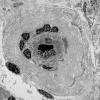

PERIPHERAL NEUROPATHY

11 VASCULITIS - VASCULOPATHY

2 Vasculopathy (4)